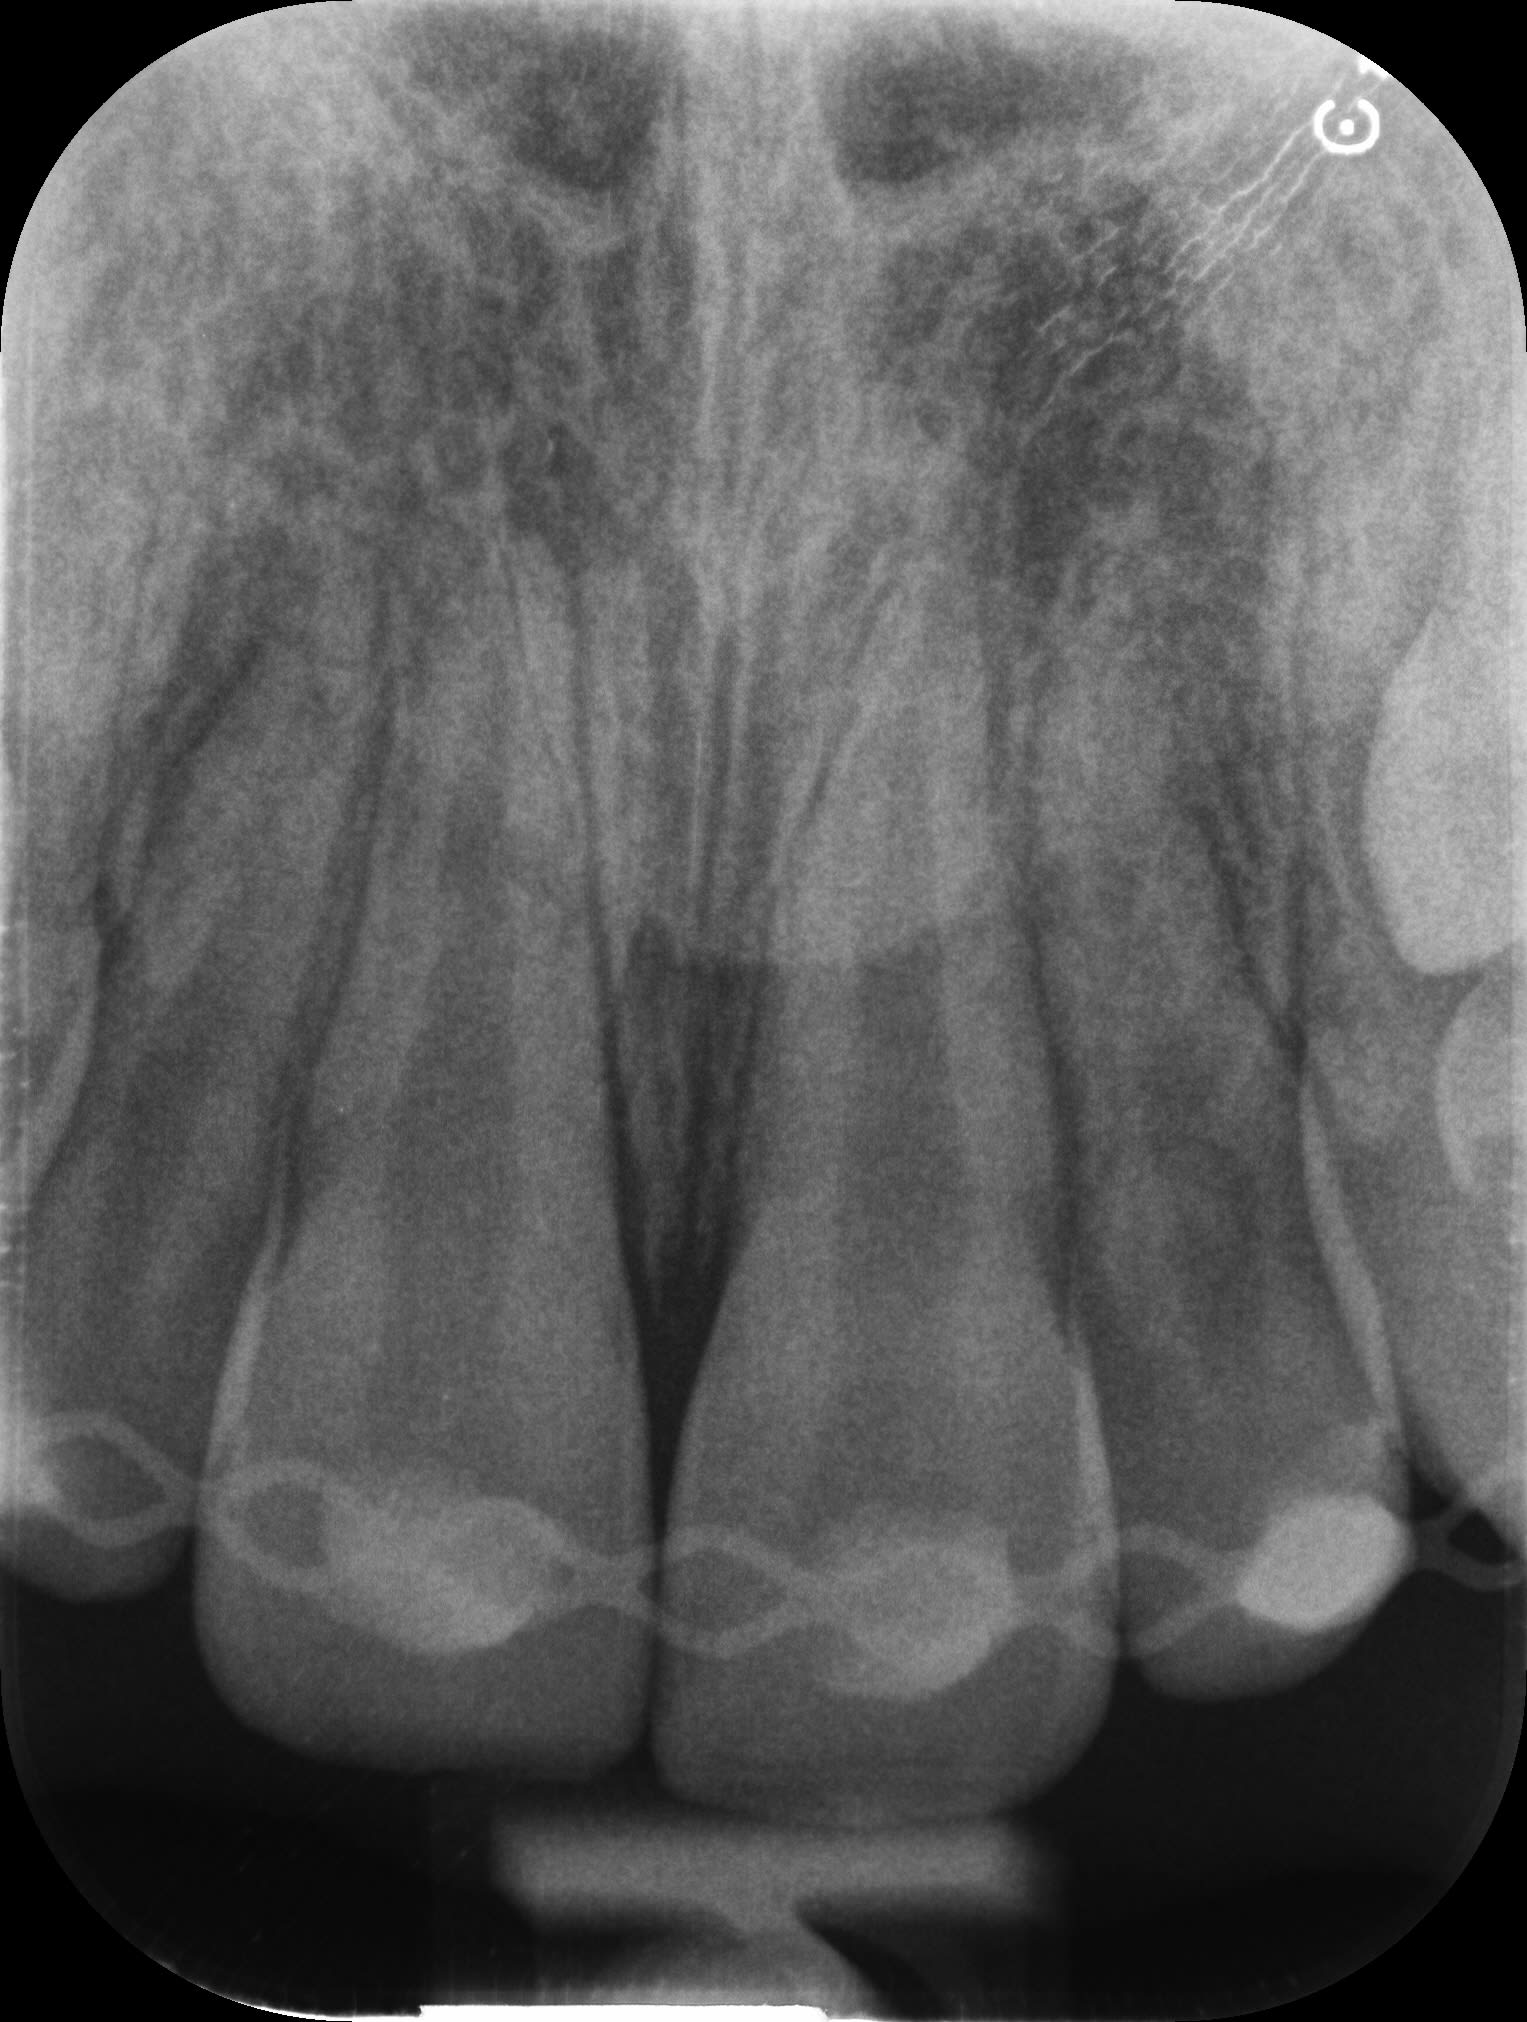

5. M1 :

- contrôle clinique et radiographique

- percussion légèrement sensible 11-21

- vitalité + 12-11-22